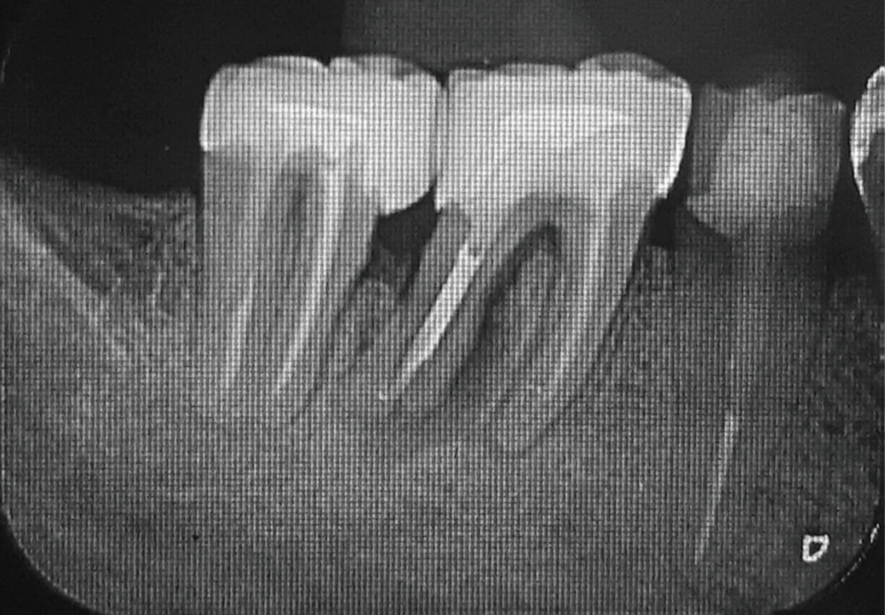

No exame clínico, a sondagem periodontal mostrou 7 mm de profundidade na distal do dente 46, com sangramento à sondagem. Para complementar o diagnóstico, a radiografia periapical do dente 46 apontou uma extensa lesão radiolúcida na raiz distal que apresentava conduto obturado, e a tomografia computadorizada de feixe cônico (TCFC) permitiu a visualização de uma tênue linha hipodensa oblíqua no terço médio da raiz distal, com aspecto sugestivo de trinca/fratura radicular (Figuras 1 e 2).